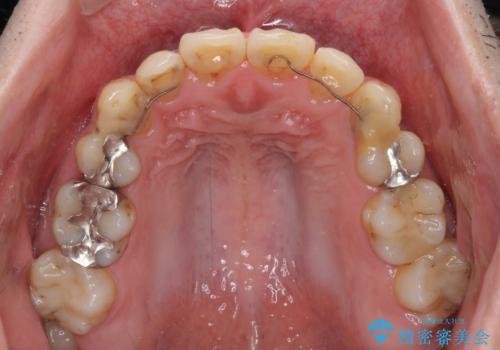

- 以前矯正を行った際に前歯が虫歯だらけとなり、審美面を気にして来院された患者様です。

虫歯の大きかった左右犬歯はオールセラミッククラウンで補綴治療をおこない、4前歯は研磨や古い充填物の詰め直しを行いました。